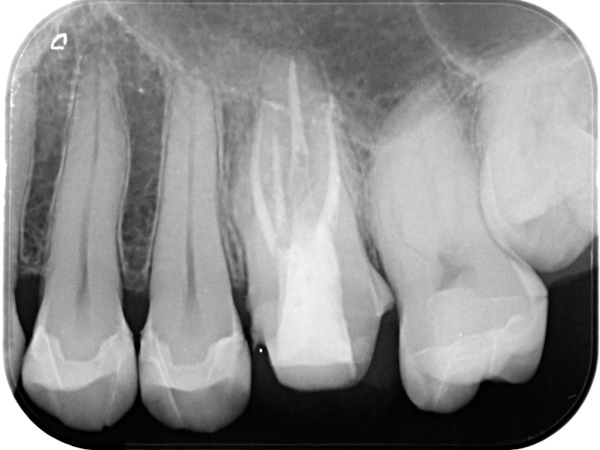

根管治療終了後3か月経過